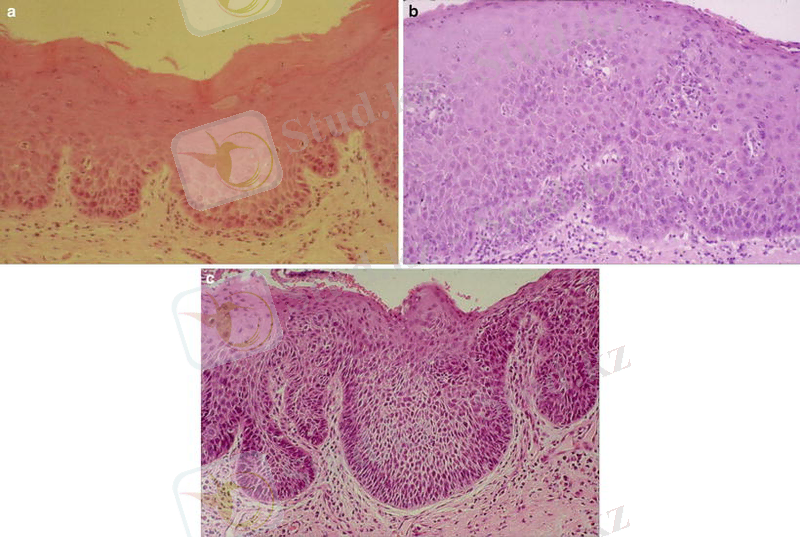

Лейкоплакия-шырышты қабат бетіндегі сүт тәрізді ағарған дақ, эпителий гиперплазия мен эпителий асты тінінің инфильтрациясы. Ары қарай тін склерозы дамиды. Жалпақ, гипертрофиялы, сүйел тәрізді болып бөлінеді. Лейкоплакия даму деңгейіне қарай жоғарыда аталған үш түрге бөлінеді. Лейкоплакия құрғақ ақ не көгеріп-ағарған қатпарлы табақша тәрізді шектелген бөліктерде немесе вульваның түгелдей бойына таралуы мүмкін. Вульва краурозы мен лейкоплакиясының бірігіп дамуы, малигнизациясы /қатерлі ісікке айналуы/ жөнінен қауіпті келеді. Бұл аурулар клиникалық белгісіз өтеді және алдын-ала қарау кезінде анықталынады. Кейде крауроз ұзаққа, көп жылға созылады, түнде қинап қышытады, ол неврозды бұзылуларға, ұйқы мен еңбек қабілеттерінің төмендеуіне әкеледі. Қышыған жерлердің орнында кішкене жарықшалар, тілінулер, соңында вульва қабынуы пайда болады. Диагноз клиникалық суреттеме негізінде қойылады. Қосымша зерттеу әдістерінен кольпоскопия, Шиллер сынағы /сыртқы жыныс мүшесін Люголь спиртті ерітіндісімен майлағанда, лейкоплакия бөліктері боялмайды/ қолданылады. Кольпоскопия кезіндегі іріктелген малигназацияға күдікті аймақтар биопсия және гистологиялық тексеруден өткізіледі.